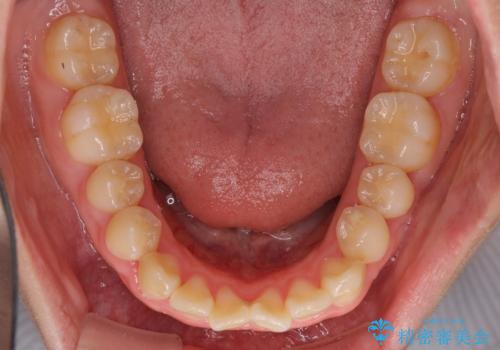

- 中学生の頃にぶつけた前歯に不格好なクラウンが装着されており、出っ歯な印象になっていることを気にして来院された患者様です。

ぶつけてしまった歯は保存が困難な状況であったので抜歯をし、ワイヤー矯正により歯列を整えつつ前歯の突出感を解消することとしました。

矯正治療後にはインプラント補綴治療を行うこととしました。

前歯の補綴治療はインプラントかブリッジかで悩んでいました。

周りの歯にむし歯がないため、インプラントがお勧めとなりますが、事故による骨欠損が大きく、歯肉ラインを整えるのが困難という問題がありました。